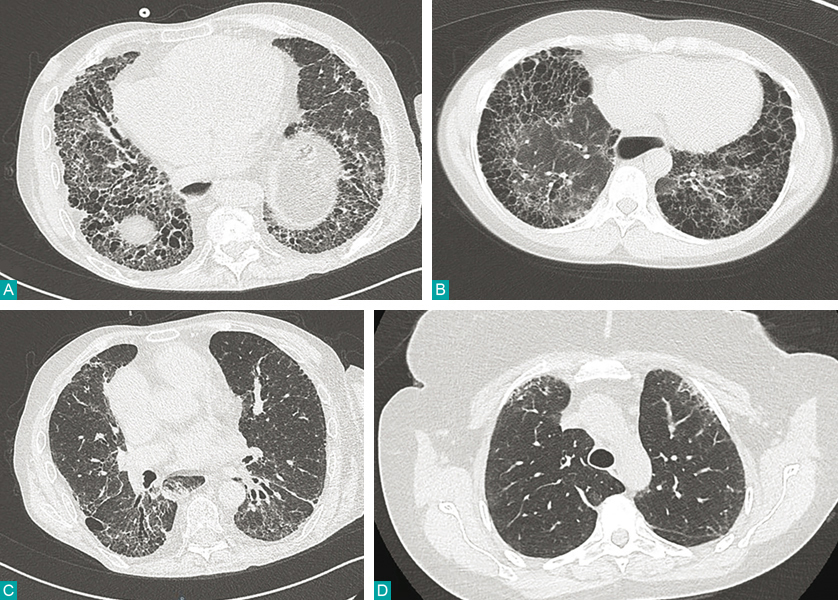

A. Aspect de fibrose des bases, bronchectasies de traction. B. Syndrome emphysème-fibrose, destruction du parenchyme pulmonaire. C. Syndrome interstitiel au stade préfibrosant avec images en verre dépoli, bronchectasie de traction. D. Syndrome interstitiel débutant avec réticulations sous-pleurales.